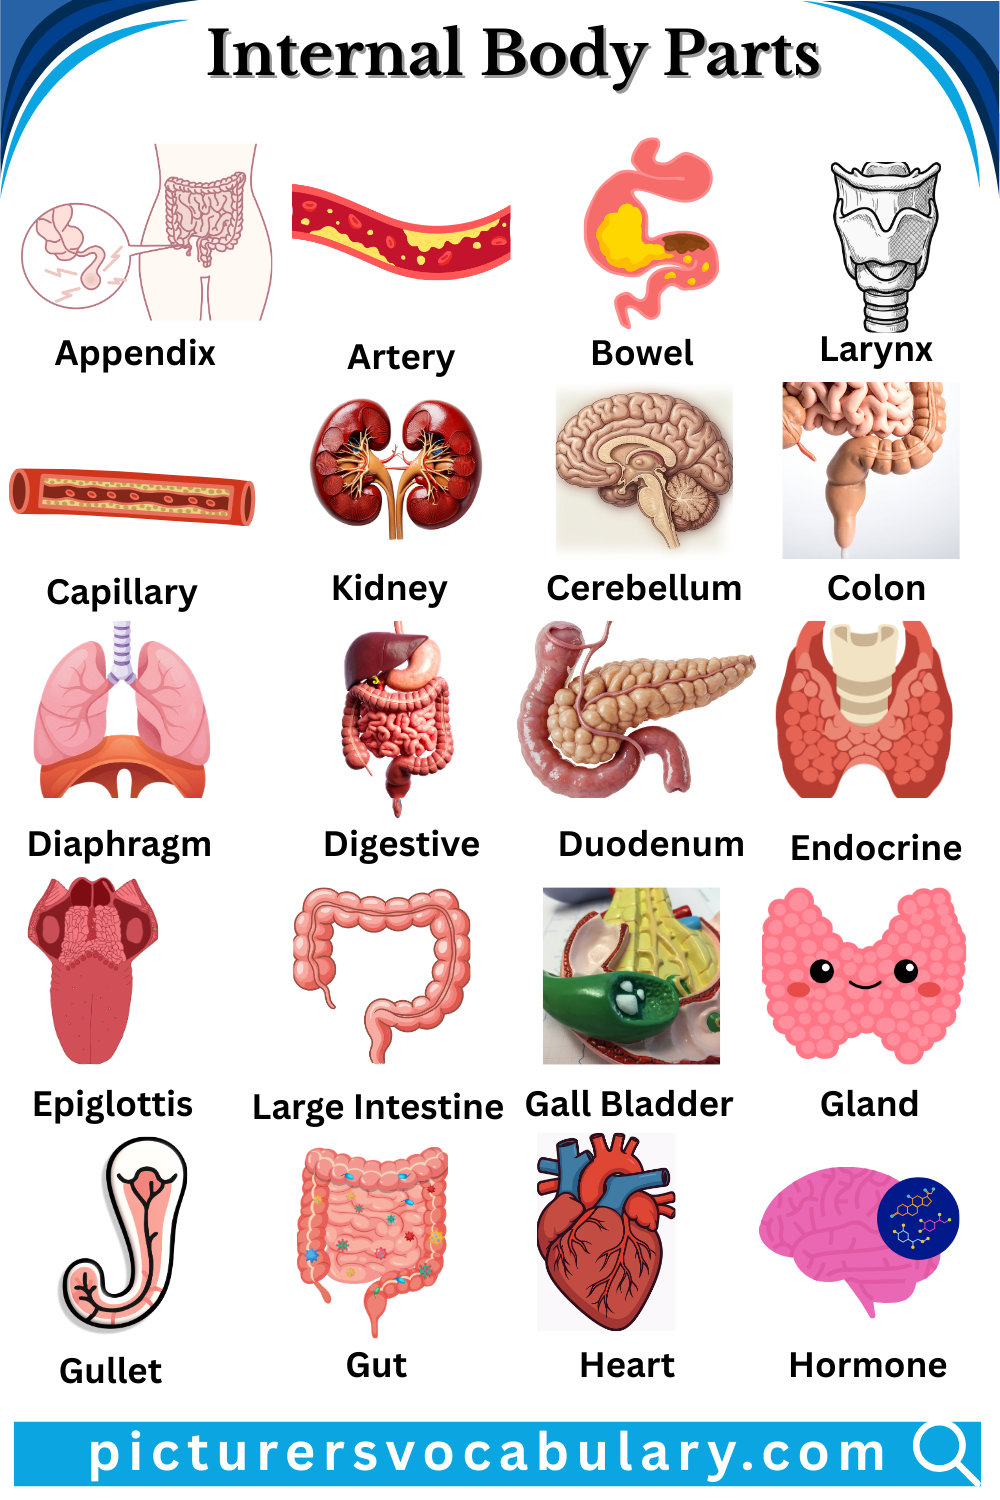

Internal Body Parts Vocabulary in English helps learners understand the organs that work inside the human body. Many of these organs cannot be seen, which makes them harder to learn and remember. Students often feel confused about their names and functions. Learning this vocabulary is important for understanding how the human body works.

This article makes learning easier by explaining internal body parts with simple meanings and clear descriptions. It introduces important organs such as the heart, lungs, brain, and stomach. Each organ has a special role that keeps the body healthy and active. By studying these words, students can improve their knowledge of human anatomy and vocabulary.

Internal Body Parts Vocabulary With Pictures

List of internal body parts is given below:-